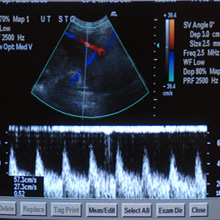

Examinarea cu ultrasunete în cel de-al doilea semestru de sarcină va indica dacă placenta este de tip previa sau nu.